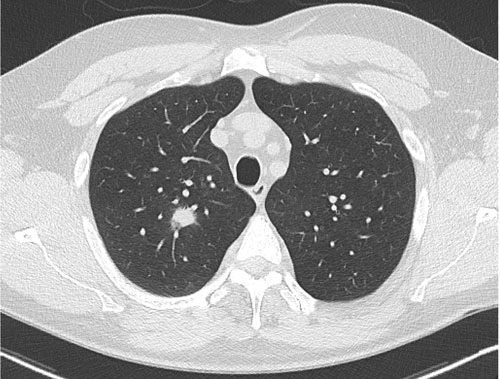

Investigations

The initial investigation of choice in secondary care remains a computed tomography (CT) scan of the chest and abdomen, followed by PET-CT scanning in those deemed suitable for potentially curative (radical) treatment, see figure 1. This is both to ensure staging is as accurate as possible and to direct diagnostic sampling.